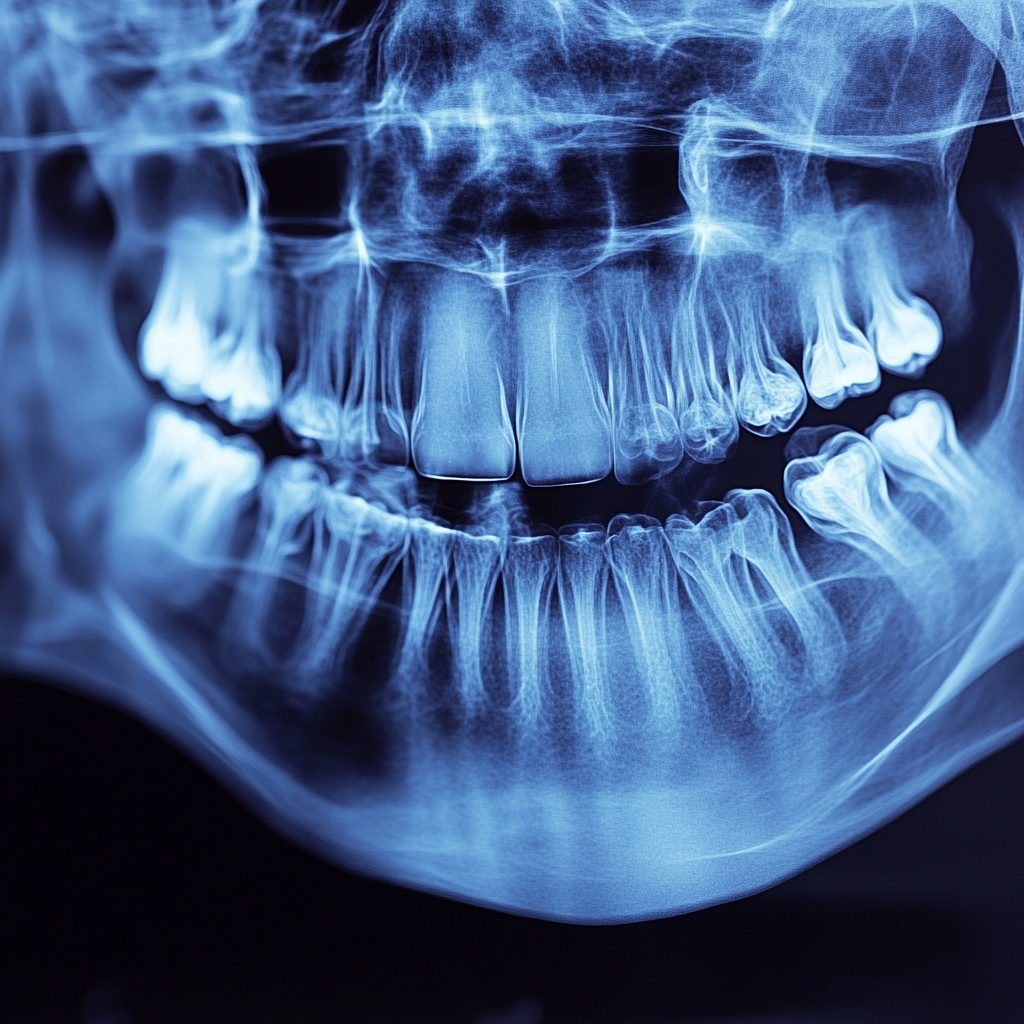

Pour ceux qui ont des implants dans la mâchoire supérieure, les problèmes de sinus peuvent être un facteur. Si un implant a été placé trop près de la cavité sinusale, cela peut entraîner des infections des sinus ou une gêne liée à la pression, en particulier si des changements se produisent dans la structure osseuse ou sinusale environnante au fil du temps.

Si des problèmes de sinus contribuent à la gêne, le traitement d’un spécialiste ORL peut être nécessaire pour résoudre l’inflammation ou les infections dans la cavité sinusale avant de procéder à des ajustements sur l’implant lui-même.